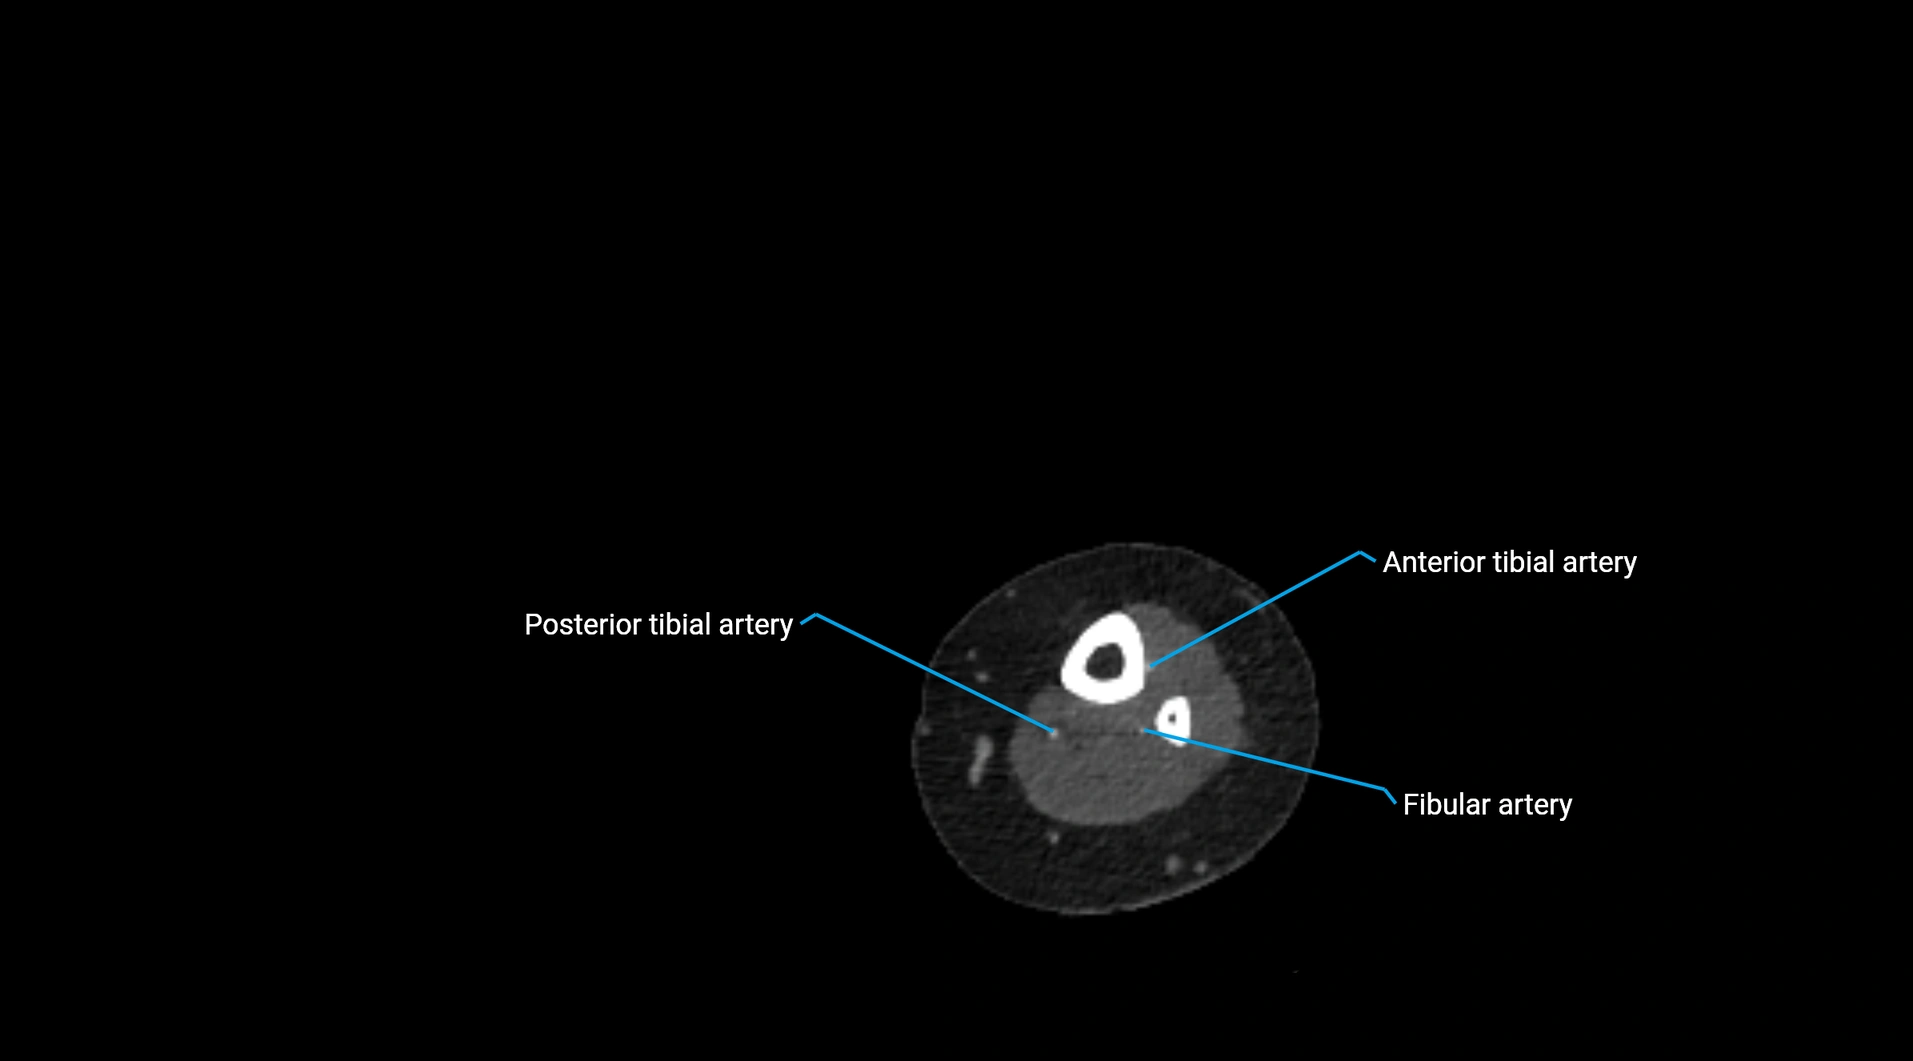

Contrast-enhanced CT (CTA):

• Gold standard for abdominal aortic imaging

• Provides excellent detail of lumen, wall, aneurysm, thrombus, and branch vessels

• Multiplanar and 3D reconstructions help in aneurysm measurement, stent graft planning, and dissection evaluation

CT images

image